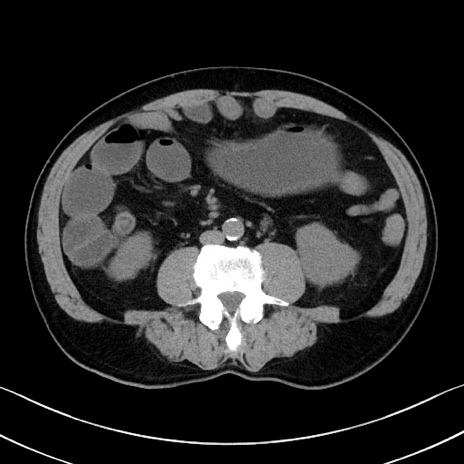

症例35(横断像)

【症例】70歳代 男性

【主訴】腹部膨満、嘔吐

【現病歴】昨日より腹部膨満感出現。本日増悪し、仙痛出現。嘔吐あり、受診。

【既往歴】糖尿病、胆摘後

【身体所見】BP 149/80mmHg、HR 74/min、BT 35.9℃、腹部:膨満、軟、圧痛なし。腸雑音減弱あり。上腹部正中切開瘢痕あり。

【データ】WBC 13500、CRP 1.72